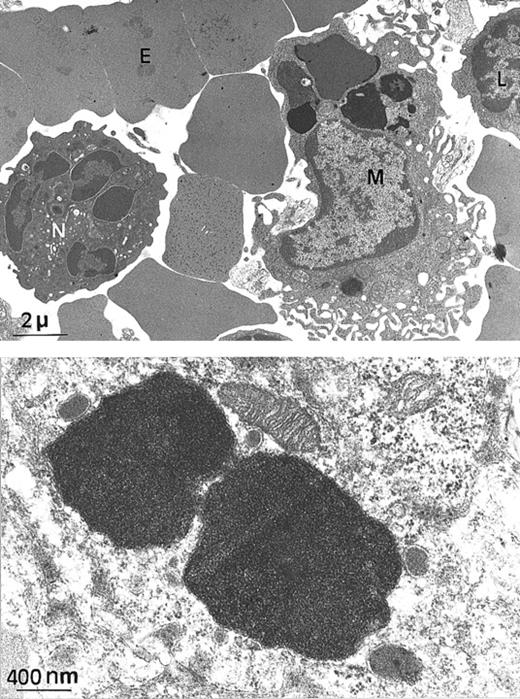

Electron microscopy of spleen from a

Fth+/− mouse. (A) At this low magnification, several spleen cells are visible, such as macrophage (M), lymphocyte (L), neutrophil (N), and erythrocyte (E). Arrows indicate electron-dense intracytoplasmic vesicles likely to contain iron (× 4000). (B) Higher magnification of 2 macrophage intracytoplasmic vesicles, showing typical paracrystalline arrangements of iron deposits (no counterstaining, × 20 000).

Since H ferritin has been shown to control the size of the labile iron pool (LIP) and to affect the IRE-IRP interactions, we explored the possibility that the Fth+/− mice, although apparently normal, might have unbalanced iron homeostasis. We intercrossed Fth+/− mice and analyzed heterozygous Fth knockout mice and their control littermates at several ages up to 45 weeks of age. These mice were of mixed C57Bl/6 × 129SV genetic background. We performed Perls staining on various tissues and quantitative measurements of tissue iron by atomic absorption spectroscopy. The amount of iron that accumulated in the liver, spleen, and heart of bothFth+/+ and Fth+/− mice increased with age during the first 3 or 4 months of postnatal development but did not noticeably differ between controls and heterozygous mice (Table 1). However, there was important variability in tissue iron among individual mice of the same age and same genotype. This might be due to C57BL/6 and 129SV iron-related genes segregating in the F2 mice. It is noteworthy that in mice, the spleen appears as a major site of iron storage since iron accumulation is readily detectable by Perls blue staining (Figure 1C, E-F), whereas it is not in the liver (Figure 1A). Ultrastructural analysis of a 25-week-old spleen shows that iron accumulates only in macrophages (Figure2A). Higher magnification of the electron-dense particles shows the typical microcrystalline array of iron deposits, surrounded by membranes (Figure 2B). There was no visible cell damage in these iron-loaded macrophages in either genotype (not shown). We also assessed the ability of the knockout mice to face an iron challenge by 3 subcutaneous injections of iron dextran over a 2-week period (30 mg total iron) into 45-week-old mice. Surprisingly, this induced massive iron loading of the liver, whereas iron deposits did not change much in the spleens (Table 1). Both genotypes developed similar iron overload. These results highlight some unusual features of iron homeostasis in mice, especially a progressive accumulation of iron in spleen macrophages, which is not modified by reduced H ferritin content.